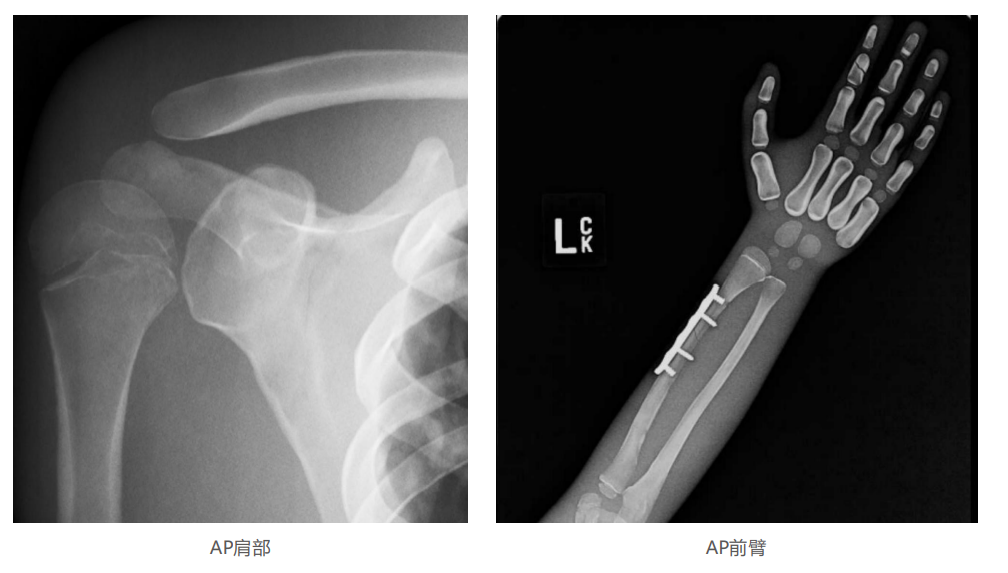

模體的大小和結構都代表了人體模體,使其便攜和易于定位。包括頭、胳膊和腿在內的整個身體。該系列包括六個部分的模體可單獨或作為一個完整的集合。

右肢有伸直或彎曲兩種配置。左臂和左腿可選伴有或不伴有內嵌骨折。

骨折版本包含最常見的人體骨折類型 ,包括脛骨扣帶骨折和腓骨普通骨折;

第一跖骨骨折;橈骨切開復位骨折 ,第二中間趾骨常見骨折。組件由適當的聚氨酯和環氧材料制成,模擬人體組織的X射線衰減特性,用于診斷和治療能量范圍(50 keV - 25 MeV) 。 材料經久耐用 ,耐沖擊,適合連續搬運。透明的軟組織有助于解剖標志的視覺指示。

? 骨骼包含皮質/小梁的區別 ,生長板和典 型的骨化;

? 半透明的軟組織使骨骼解剖形象化;

? 左附件五種最常見的骨折;